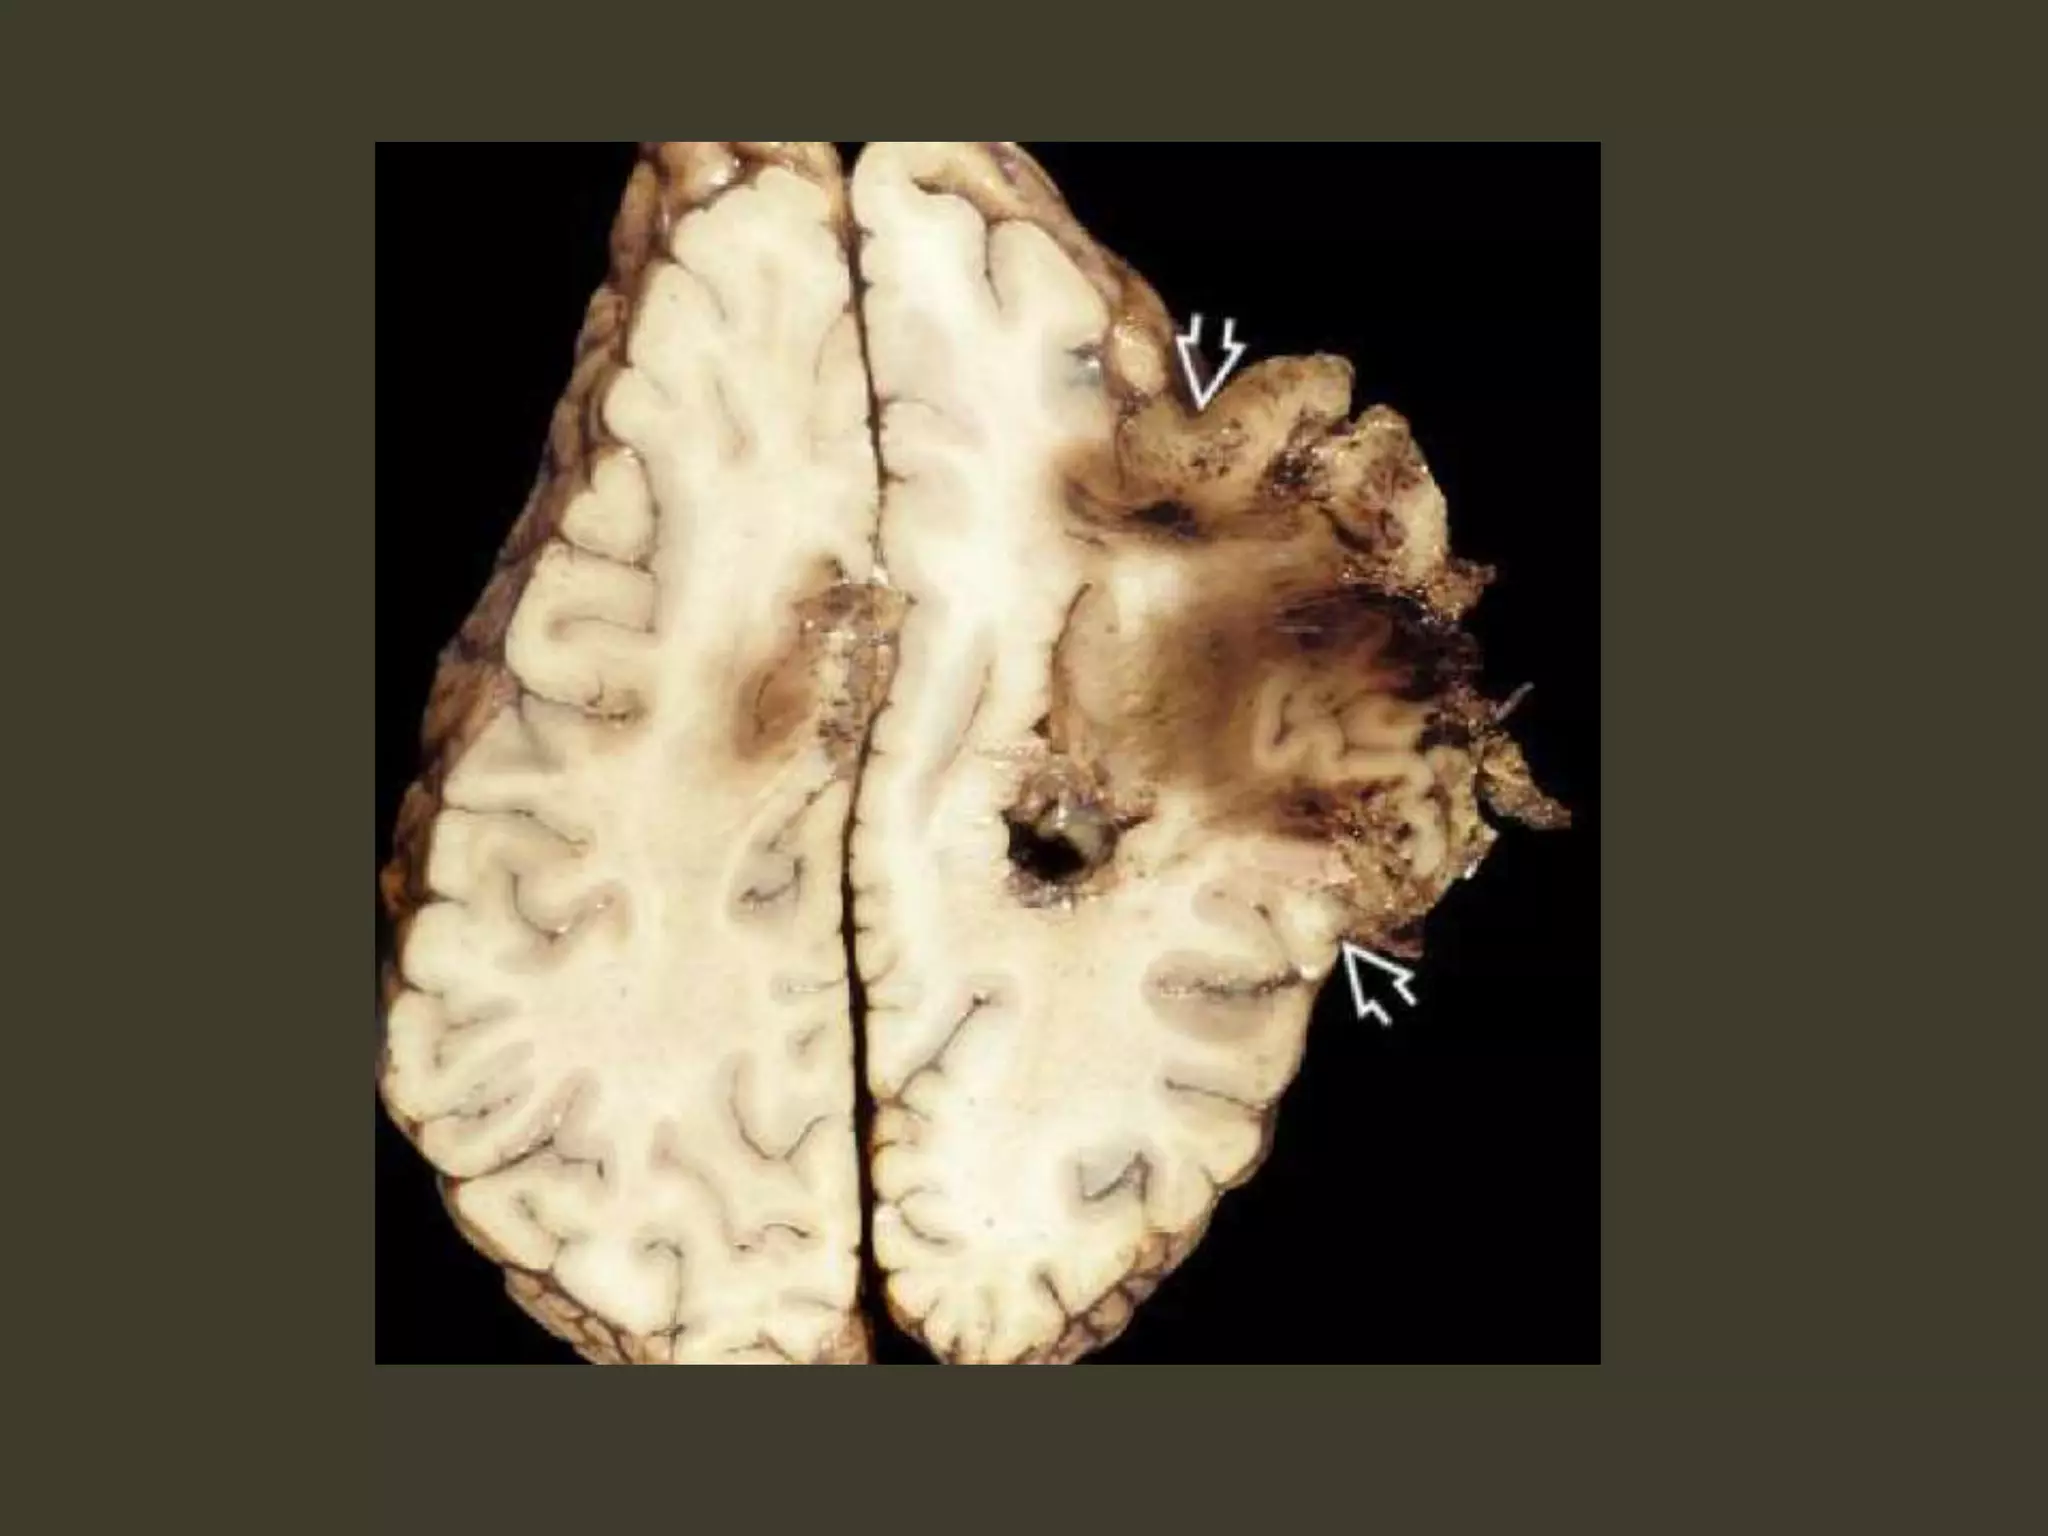

Duret hemorrhage

"Top-down" mass effect displaces the midbrain

inferiorly

closes the midbrain-pontine angle

Perforating arteries from basilar artery

are compressed and buckled

hypothalamic and basal

ganglia infarcts

complete bilateral DTH

perforating arteries from the

circle of Willis compression against the

central skull base

hypothalamic and basal ganglia

infarcts